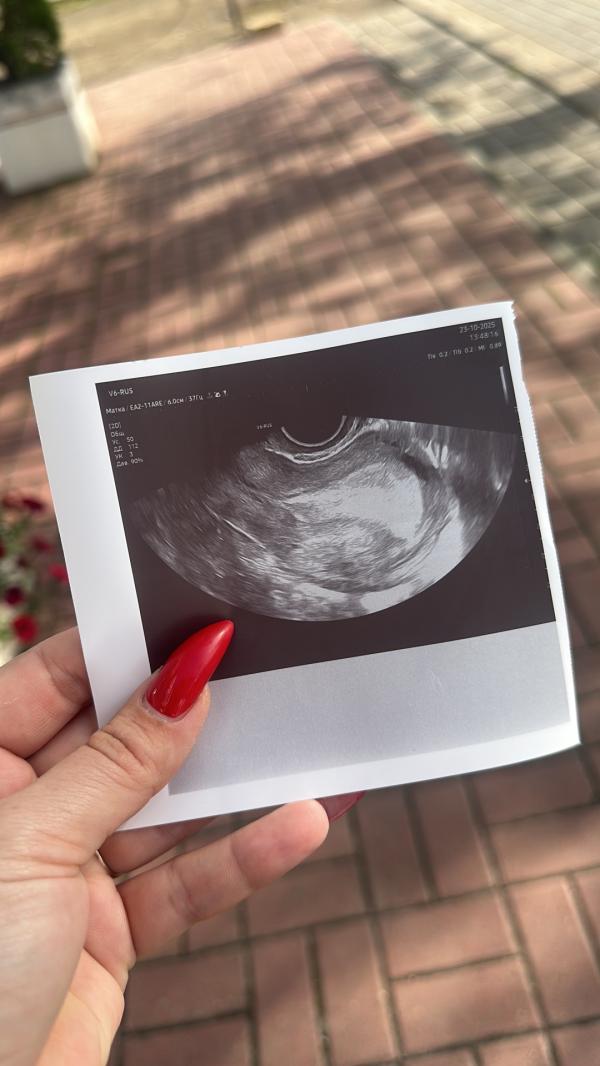

У меня шок…почему по узи нет эмбриона?завтра должны пойти месячные,тест показал беременность 1-2нед..😭😭😭😭сдала хгч..

Для узи должно быть 3 недели беременности,а не 1-2 недели. Конечно у вас ни чего не увидели🤷🏼♀️

У меня сегодня 4,6 нед не нашли плодного яйца, задержка почти неделя, но мне узист сказал, что возможно еще не спустилось

Молодцы, что сходили на узи. Подтвердили маточную для вашего спокойствия🙏

Вы рано ждете эмбрион. После 1000 хгч только только можно найти плодное яйцо. После этого желточный мешочек, и только потом эмбрион. И то не факт, что сб сразу поймают

Вы видимо имеете ввиду плодное яйцо? Эмбриона в принципе ещё не может быть. Плодное яйцо рано, темболее тест показал 1-2 недели. После 4х недель будет видно плодное яйцо. После 6-7 недель эмбрион!

На узи появится только когда хгч более 1000 ед. Вы просто рано пошли) Повторите узи минимум через неделю и тогда ваша бусинка будет уже на месте.